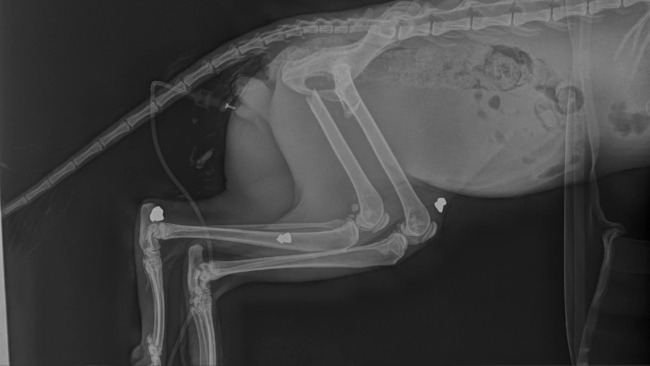

Na zdjęciu poniżej najlepiej widać miejsca gdzie jest śrut, jakoś zwyrodnialec postanowił sobie postrzelać do kota...

Na zdjęciu poniżej najlepiej widać miejsca gdzie jest śrut, jakoś zwyrodnialec postanowił sobie postrzelać do kota...

Gdy udało sie ustabilizować jego stan, na rtg wyszedł rozmiar obrażeń, dwie złamane łapki tylna i przednia, przpuklina pachwinowa, w którą już wchodzą jelita, braki w uzębieniu, trochę płynu pourazowego w jamie brzusznej oraz co najbardziej szokujące śrut w łapkach, czyli dodatkowo jeszcze strzelano do niego :(